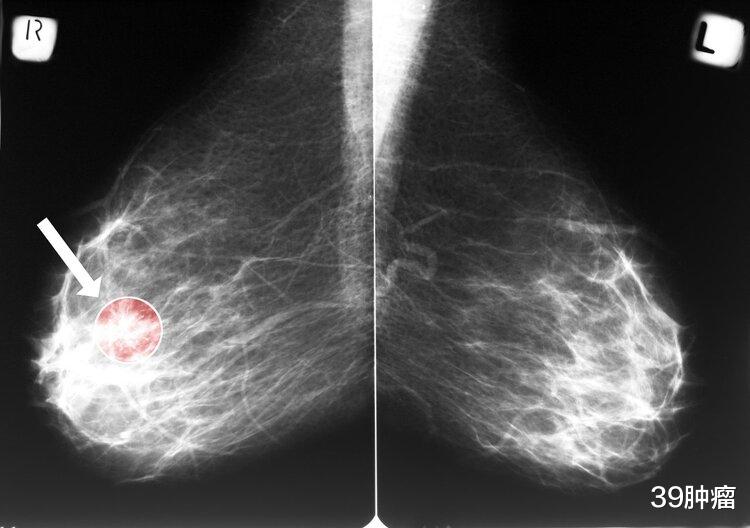

?3.乳腺肿块

乳房内出现肿块是乳腺癌最为典型的症状之一 , 临床上约有90%的患者是因为该情况入院就诊 。 此类肿块一般有位置固定、活动度差、边界不清楚以及发展迅速等特点 。